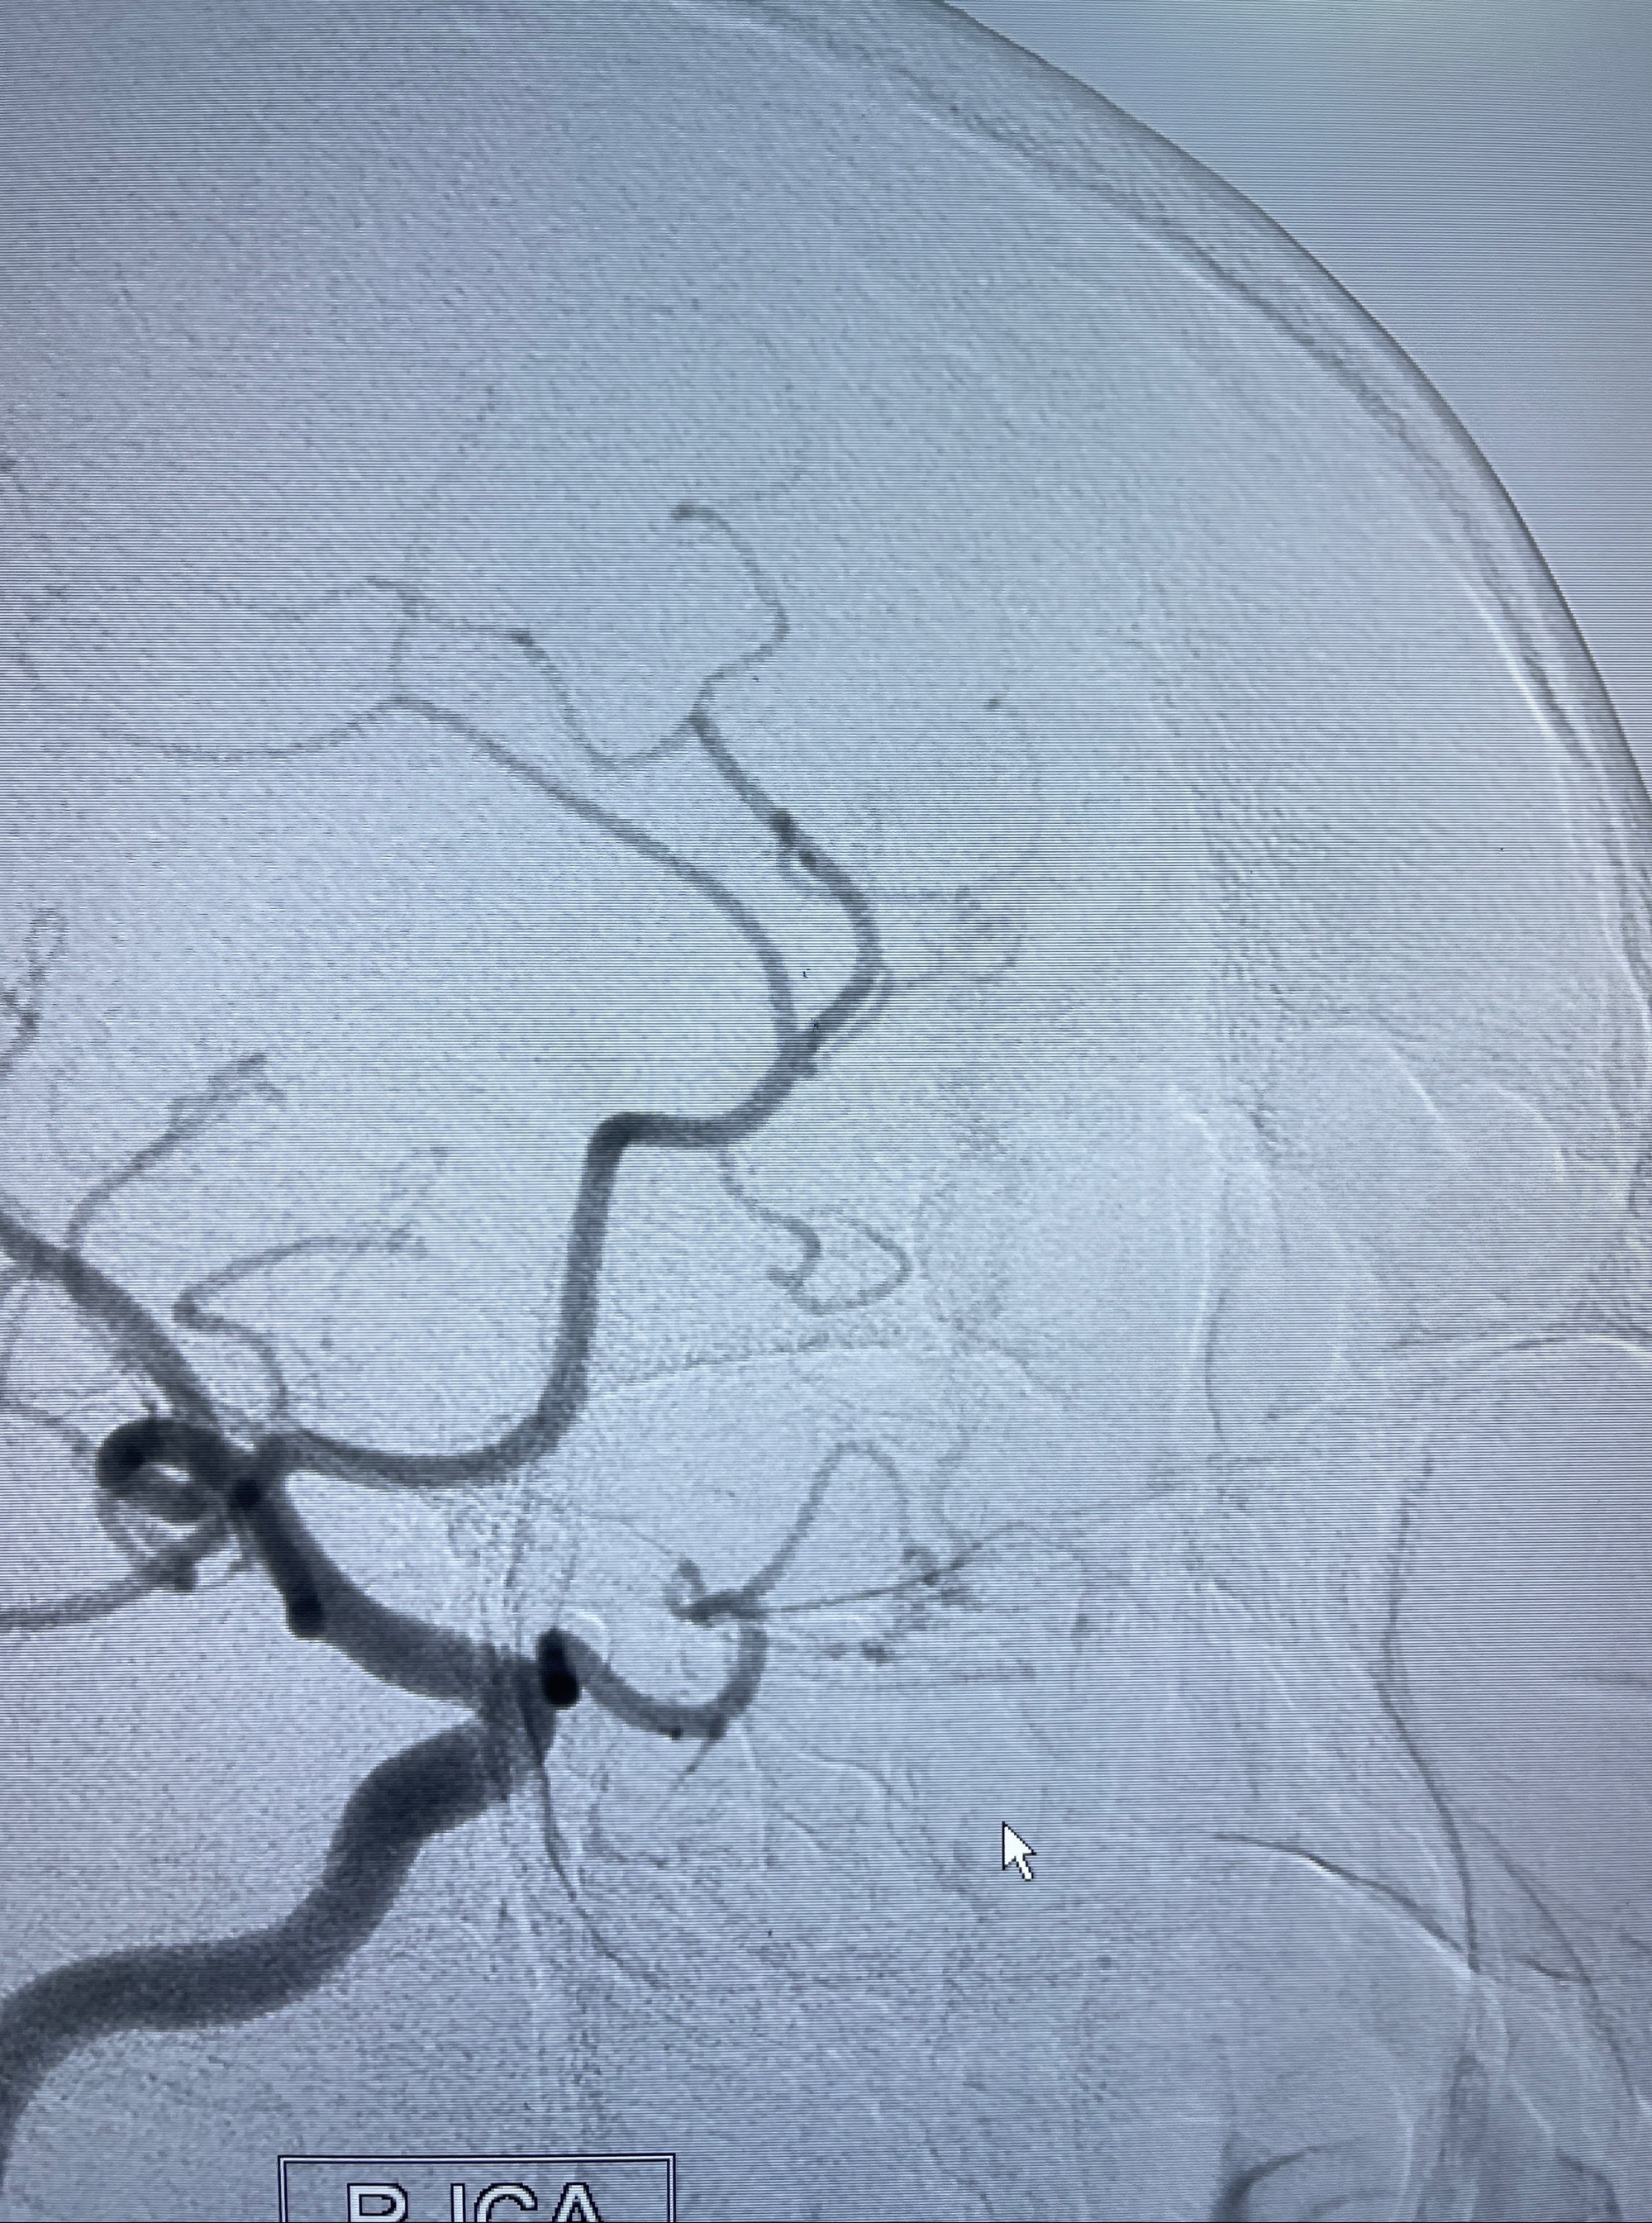

2023年8月21日]景德镇市第一人民医院脑血管造影检查,提示:主动脉弓、双侧颈总动脉、锁骨下动脉造影未见异常,左侧大脑前动脉静脉瘘。

2023-09-13全脑血管造影:前颅底硬脑膜动静脉瘘,供血动脉为双侧胼周动脉、眼动脉脑膜支,静脉向上矢状窦方向引流